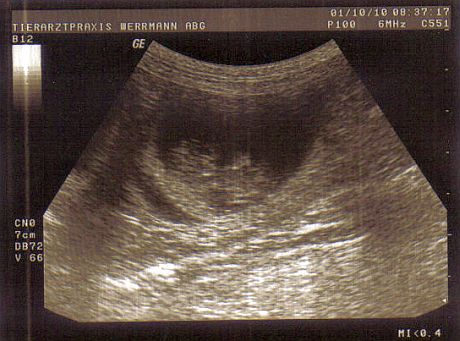

Auf diesem Bild ist sehr klar die Fruchtblase mit dem darin liegenden Welpen zu erkennen. Der Welpe ist 31 Tage alt und scheint auf dem Rücken zu liegen.